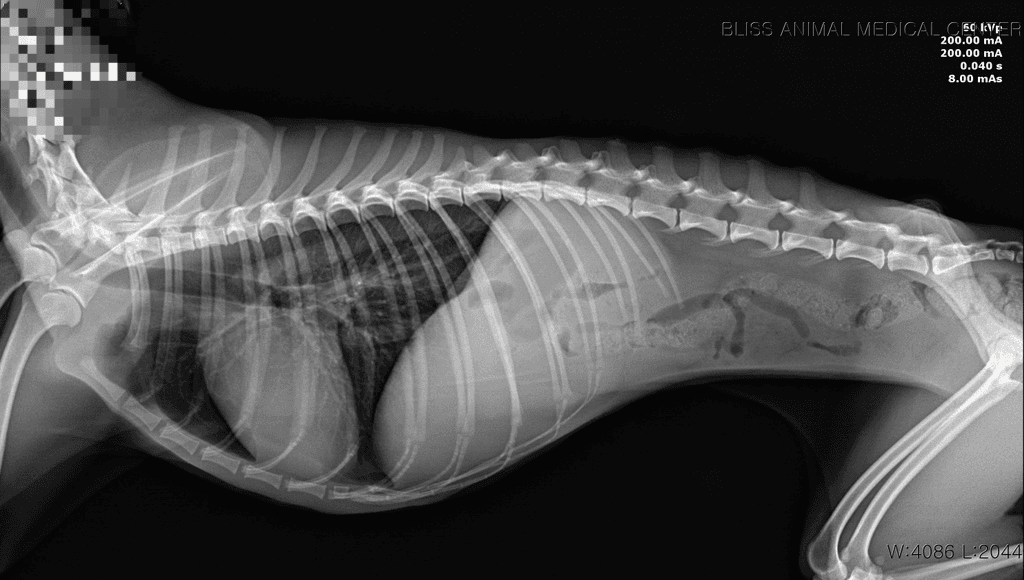

7월 16일에 강아지가 무기력하더니, 17일 새벽에 1번, 병원에서 2번, 내원 후 집에서 1번 총 4번 발작했습니다. 검사해 보니 췌장염도 있고, 심장병(단계 설명은 못 들음), 간 문제 등등 그 외에도 문제가 많이 보여서 수의사 님도 정확히 뭐 때문에 발작을 했는지 확답을 내리지 못 하셨습니다.

이 나이에 이렇게 아픈 것도, 체격/먹는 거에 비해 살이 안 오르는 것도 선천적 요인일 가능성이 높다고 하셨습니다.

주치의 선생의 의견과 비슷하게 현재 발작을 유발할정도의 수치들은 아닙니다.

이런 상황이라면 뇌 외성 원인을 잠정적으로 배제할 수 있는 수준이라 뇌외성 이상 즉, 두개골 내의 이상을 평가하기 위한 MRI 검사가 추천됩니다.

뇌내 이상은 혈액검사에서 특별한 변화를 보이지 않거나 위 자료처럼 애매하게 나오는게 일반적이기 때문입니다.